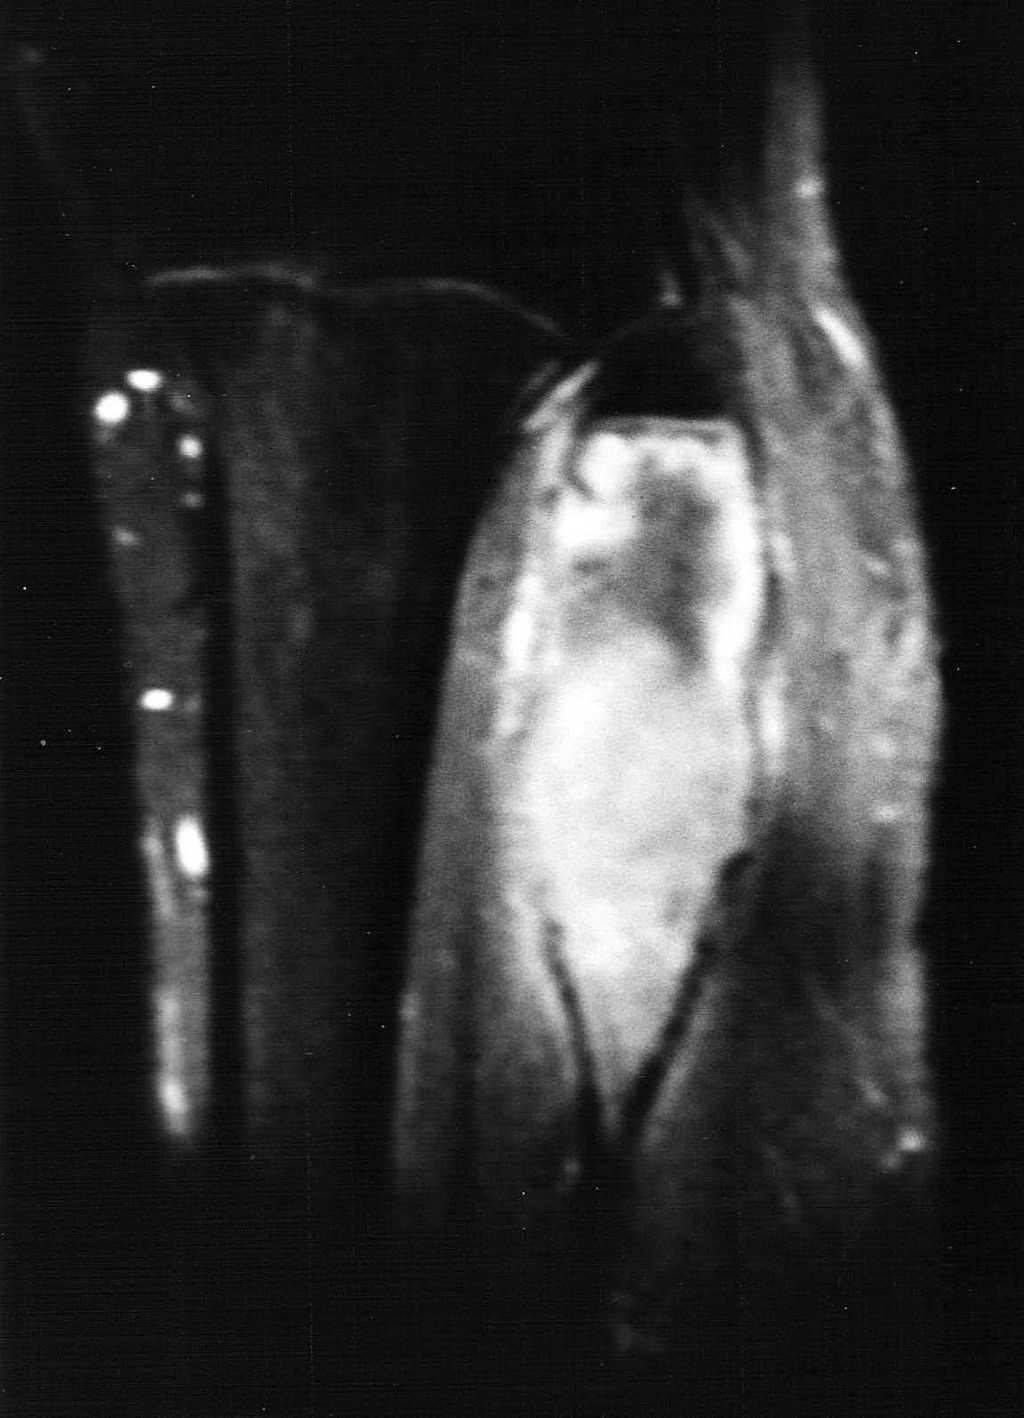

Paciente varón de 15 años, que fue remitido a consultas de traumatología por genu valgo. No tenía antecedentes de interés, salvo crisis asmáticas en la infancia, y la presencia de una lesión lítica ya conocida en el peroné, que sugería el diagnóstico diferencial de displasia fibrosa o quiste óseo aneurismático como primeras posibilidades. La lesión parecía haber crecido respecto a estudios previos. En la radiografía simple (fig. 3), se identificaba una gran lesión lítica expansiva que afectaba predominantemente a la metáfisis proximal del peroné derecho, extendiéndose caudalmente a la diáfisis, y limitada superiormente por la placa de crecimiento. No tenía matriz ósea interna y la zona de transición, al menos en la zona inferior, era estrecha. En el interior presentaba un patrón de múltiples septos con cierto adelgazamiento endostal. En la TC (fig. 4) la cortical estaba muy adelgazada, con focos de discontinuidad sin identificar masa de partes blandas, y presentaba finos septos internos. Se realizó un estudio mediante RM con un equipo de 1,5T (Gyroscan Philips Intera). En la RM el tamaño aproximado de la lesión era de 8,5 x 3,3 x 3 cm (craneocaudal x anteroposterior x lateromedial). La lesión insuflaba el peroné sin visualizar masa de partes blandas. En la secuencia T1-ES (TR/TE 460/15) se comportaba hipointensa de forma homogénea (fig. 5). En la secuencia STIR (1688/15) (fig. 6) parecía tener dos componentes, con diferentes intensidades de señal. El superior hipointenso y el inferior levemente hiperintenso. En la secuencia dinámica T1 (TR/ TE 460/15) tras gadolinio itravenoso (figs. 7 y 8) presentaba un leve realce periférico del componente superior en fase tardía con prácticamente nulo realce en fase precoz y, sin embargo, un intenso realce del componente inferior en fase precoz, seis segundos después de que el contraste se identificase en el interior de los vasos arteriales, con realce persistente en fase tardía (fig. 9). Se realizó una gammagrafía ósea de cuerpo completo en proyecciones anterior y posterior en tres fases. En la fase vascular se observaba un incremento en la llegada del radiotrazador del pool sanguíneo a la región proximal del peroné derecho. La imagen tardía mostraba una hipercaptación en el extremo proximal de dicho hueso. Descartaba la posibilidad de quiste óseo, que no suelen mostrar captación en la gammagrafía y aconsejaban descartar otro tipo de tumoración ósea. No se visualizaron otras lesiones a distancia. En estos momentos el diagnóstico diferencial propuesto fue de fibroma condromixoide, fibroma desmoplásico y quiste óseo aneurismático, a pesar de la ausencia de niveles líquido-líquido. A continuación se realizó una biopsia abierta, con diagnóstico de fibroma desmoplásico. En el estudio macroscópico se identificaban varios fragmentos blanquecinos de consistencia ósea. En el estudio microscópico, se identificó una proliferación de células elongadas, separadas de abundantes fibras de colágeno. La densidad celular era muy variable en función del campo estudiado, lo mismo que la disposición de las fibras de colágeno, bien onduladas o con gran laxitud. Las células tenían núcleos ovoideos, sin aparentes nucleolos y sin figuras mitóticas. Algunos de los remanentes óseos atrapados en la muestra tenían actividad osteoclástica, sin ver en ningún momento atipias.

Fig. 5.--Secuencia coronal T1-ES. La lesión aparece homogéneamente hipointensa, de comportamiento expansivo, limitada superiormente por la phisis.

Fig. 6.--Secuencia STIR coronal. Se diferencian los dos componentes. El superior hipointenso con una halo de hiperseñal y el inferior hiperintenso sin asociarse a masa de partes blandas.

La RM permite una clara delimitación entre el hueso normal y el tumoral. Generalmente aparece hipointenso tanto en las secuencias T1 como T2, como los linfomas o los tumores fibrosos, debido a la densa matriz conectiva, y para algunos autores debido a la relativa hipocelularidad, lo que significa una disminución de los protones móviles6. Otros autores recogen otros hallazgos, como la presencia de una pseudocápsula, focos de necrosis, niveles líquido-líquido dentro del tumor8 y, en ocasiones, un comportamiento hiperintenso en las secuencias T22,4. En nuestro caso se identificaban dos componentes diferentes dentro de la misma lesión de diferente señal en las secuencias T2. El componente superior es hipointenso y el inferior de intensidad intermedia. En las secuencias dinámicas postgadolinio intravenoso, el componente superior mostraba un leve realce periférico en fase tardía con prácticamente nulo realce en fase precoz y el componente inferior presentaba intenso realce en fase precoz, que persistía en fases tardías.